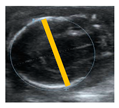

The BPD, CC, and AC of fetuses were measured using ultrasound in guinea pigs from G25 until term. This analysis revealed that BPD, CC (perimeter), and AC (perimeter) increased along with gestational age and conformed to a second-order polynomial (quadratic) curve, all with high determination coefficients (Figure 1A,B,D). Fetal CC (area) and AC (area) also increased with gestational age; however, these parameters fitted to a first-order polynomial (straight line) curve (Figure 1C,E).

Figure 1.

Fetal biometry across pregnancy. Guinea pig fetal (A) biparietal diameter (BPD), (B) cranial circumference (CC), (C) cranial area (CA), (D) abdominal circumference (AC), and (E) abdominal area (AA), and their best fit from gestational day 25 to the end of pregnancy. Each dot represents an individual measurement (n = 47 from 19 litters). Black line = data best fit. Magenta dashed lines = 95% CI.